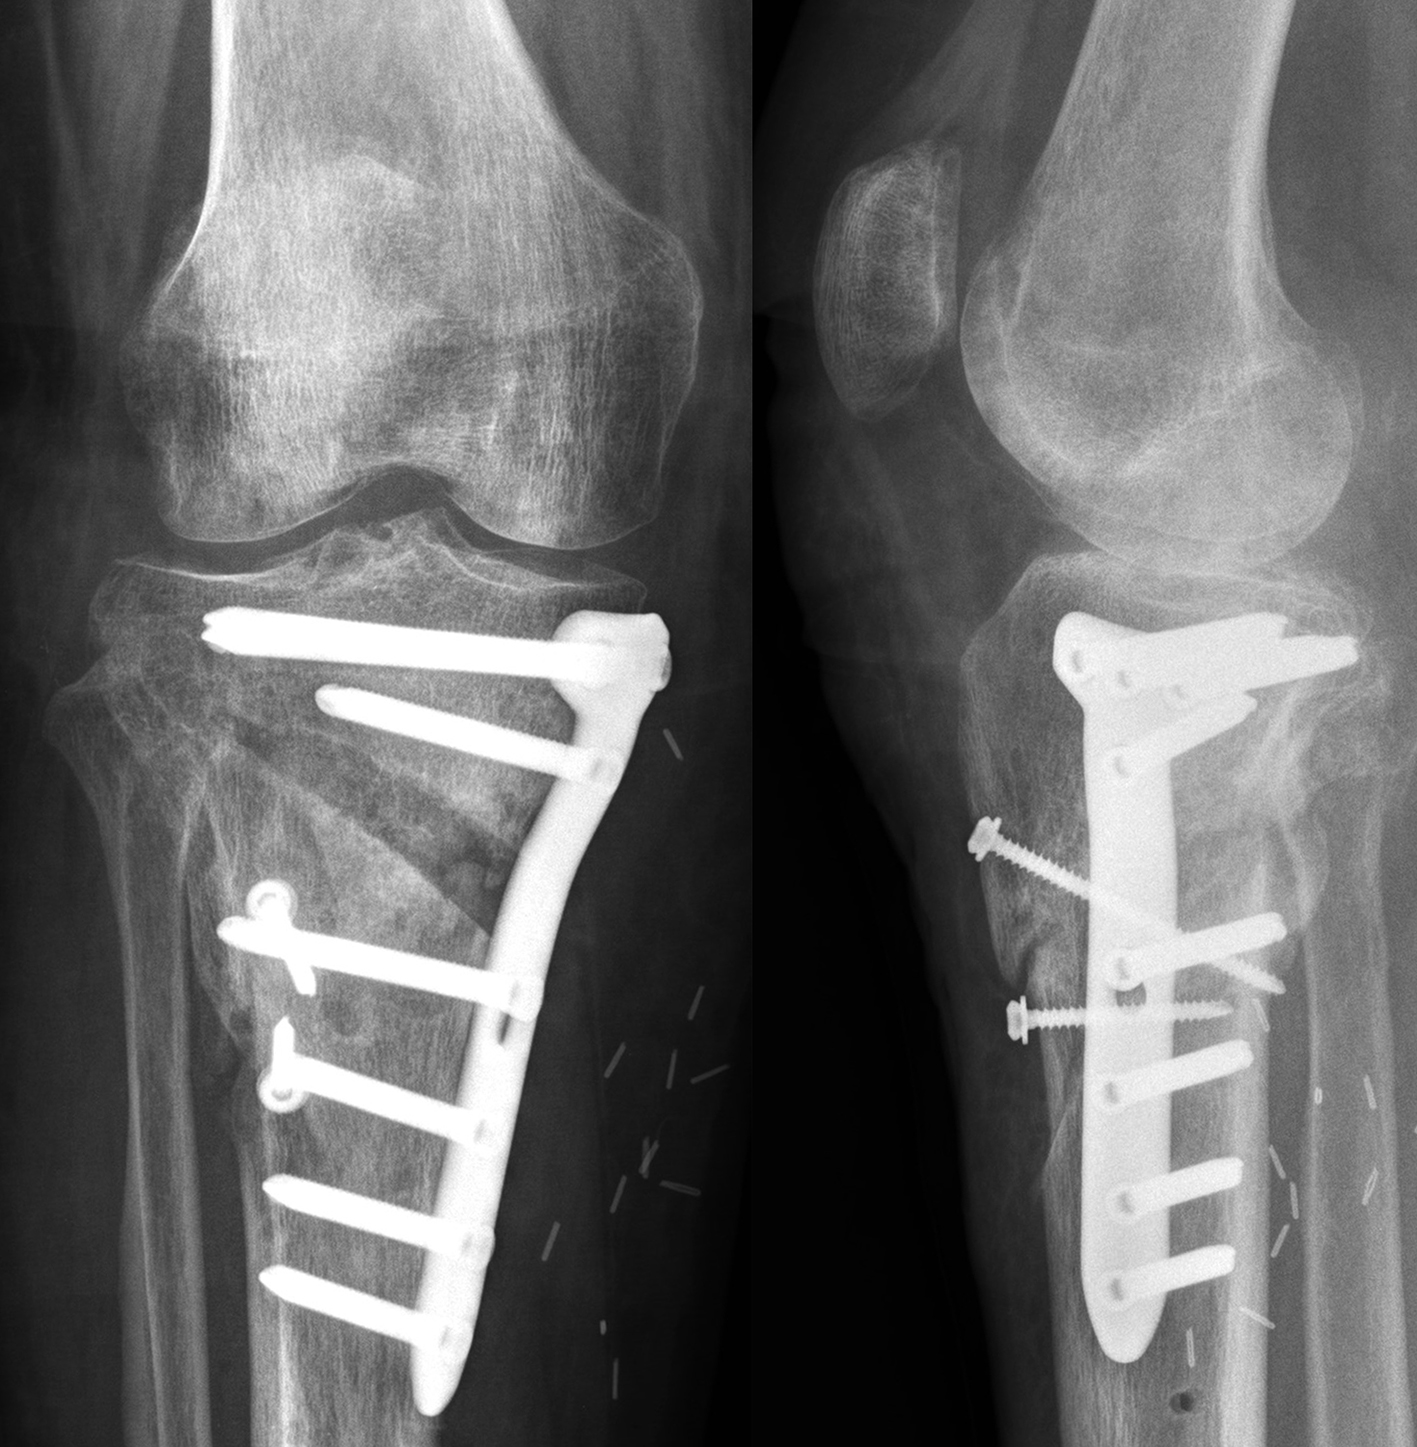

The TomoFix Anatomical Medial High Tibial Plate is contoured to provide an anatomical fit. When compared with the TomoFix Standard and small plates, the new design is intended to reduce both implant prominence

and postoperative implant irritation. Fig 1 shows x-rays from one patient.